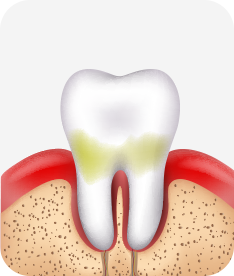

건강한 상태

치아 주위의 잇몸이 핑크색을 띄며, 잇몸에서 피가 나지 않음.

스케일링을 6개월 ~ 1년 주기로 받고 올바른 칫솔질로 건강한 치주 조직을 유지

치은염 (초기~중기)

치아 주위의 잇몸이 붉게 부어 있으며, 칫솔질 등을 할 때 피가 남.

스케일링 주기의 조절이 필요할 수 있으며, 올바른 칫솔질을 시행하여야 함.